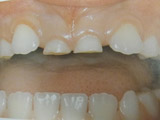

Υπενασβετίωση της αδαμαντίνης

Συνήθως εκδηλώνεται με λευκές, κίτρινες ή καφέ κηλίδες στους τομείς και τους γομφίους, μπορεί όμως να επηρεάσει και άλλα δόντια. Η κλινική εικόνα μπορεί να περιορίζεται μόνο στην εμφάνιση αυτών των κηλίδων, ή να είναι πιο σοβαρή προκαλώντας απώλεια της αδαμαντίνης του δοντιού, με συνέπεια την εμφάνιση ευαισθησίας και πόνου καθώς και τερηδόνας.

Η κατάσταση αυτή της αδαμαντίνης οφείλεται σε διαταραχή της διάπλασής της με αποτέλεσμα την ελλιπή ενσωμάτωση των μετάλλων στη δομή της. Έχουν ενοχοποιηθεί διάφοροι παράγοντες (περιβαλλοντικοί, ασθένειες της μητέρας και του βρέφους, διατροφή κ.ά.) οι οποίοι μπορούν να προκαλέσουν αυτές τις διαταραχές.

Σημαντική είναι η έγκαιρη διάγνωση από τον παιδοδοντίατρο και η εφαρμογή ενός ολοκληρωμένου προληπτικού προγράμματος προστασίας αυτών των δοντιών προκειμένου να διατηρηθούν υγιή.